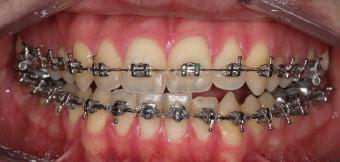

closed.

21Dental Tribune Bulgarian Edition / октомври 2022 г. ДИАГНОСТИЧНИ РЕЗУЛТАТИ: 1. Възраст на пациента: 21 години 2. Скелетен клас III (ANB 0) 3. Зъбен клас 3 4. Ръбцова захапка във фронта, кръстосана в дисталните участъци 5. Тясна горна челюст 6. Overjet – 0 мм, Overbite – 0 мм 7. Несъответствие на горната с долната средна линия 8. Единични контакти в ЦО 9. Хиподивергентен тип на растеж SN/MP – 33.5 10. Неравен гингивален контур 11. Неравна линия на усмивката 12. Тенденция за рецесии в долен фронт ПРЕПОРЪЧИТЕЛНО ЛЕЧЕНИЕ: Пълно ортодонтско лечение с метални брекети „Алекзандър“ Корекция на клас 3 захапката в областта на кучешките зъби с екстракция на първите пре молари в долна челюст Корекция на кръстосаната захапка в дистални участъци Коригиране на ръбцовата захапка във фронта Подобряване на ОJ и OB на пациента Стрипинг в долен фронт Подреждане на зъбите в горната и долната челюст Професионално хигиенизиране и профилактични дентални прегледи са препоръчителни на всеки 6 месеца. 1-ви месец След 1 месец са залепени брекети в горната челюст – поставена е еластична дъга. 016 NiTi. В долната челюст са елиминирани ротациите, поставена е стоманена дъга. 016SS, закалена с ток, и еластична верижка за затваряне на пространствата. 3-ти месец В долната челюст е поставена трета дъга – 17 x 25 NiTi с къси лигатури и верижка

В горната челюст се затварят пространствата с дъга .016SS и верижка. 5-и месец На 5-ия месец след залепяне на брекетите в долната челюст е поставена стоманена дъга 16 x 22 SS с четвъртито сечение, омега луп и тай бек. В горната челюст е поставена дъга 17 x 25 NiTi. Поради липсата на стабилни оклузални контакти са поставени лингвални верижки в областта на моларите, за да се предотврати нежелана ротация на 7-ите зъби. 6-и месец На 6-ия месец от началото на лечението са екстрахирани долните първи премолари, поставена е дъга 16 x 22 SS със затваряща чупка teardrop. Чупката се активира всеки месец по 1 мм с чинч-бек. клиничен случай | ортодонтия СТЪПКИ НА ЛЕЧЕНИЕТО Начало на лечението Лечението започва с поставяне на апарат за бърза експанзия в горната челюст. През първия месец от лечението са направени 24 оборота на апарата за експанзия. Залепени са брекети в долната челюст, поставена е дъга 17x25 CuNiTi, като са предпи сани клас 3 ластици (1/4”,4 1/2 oz) по време на сън, за да се осигури контрол върху торка на долните резци. Фиг. 2а Фиг. 3a Фиг. 4a Фиг. 3b Фиг. 4b Фиг. 3c Фиг. 4c Фиг. 3d Фиг. 4d Фиг. 3e Фиг. 4e Фиг. 5a Фиг. 5b Фиг. 5c Фиг. 5d Фиг. 5e Фиг. 6a Фиг. 6b Фиг. 6c Фиг. 6d Фиг. 6e Фиг. 7a Фиг. 7b Фиг. 7c Фиг. 7d Фиг. 7e Фиг. 2b Фиг. 2c Фиг. 2d